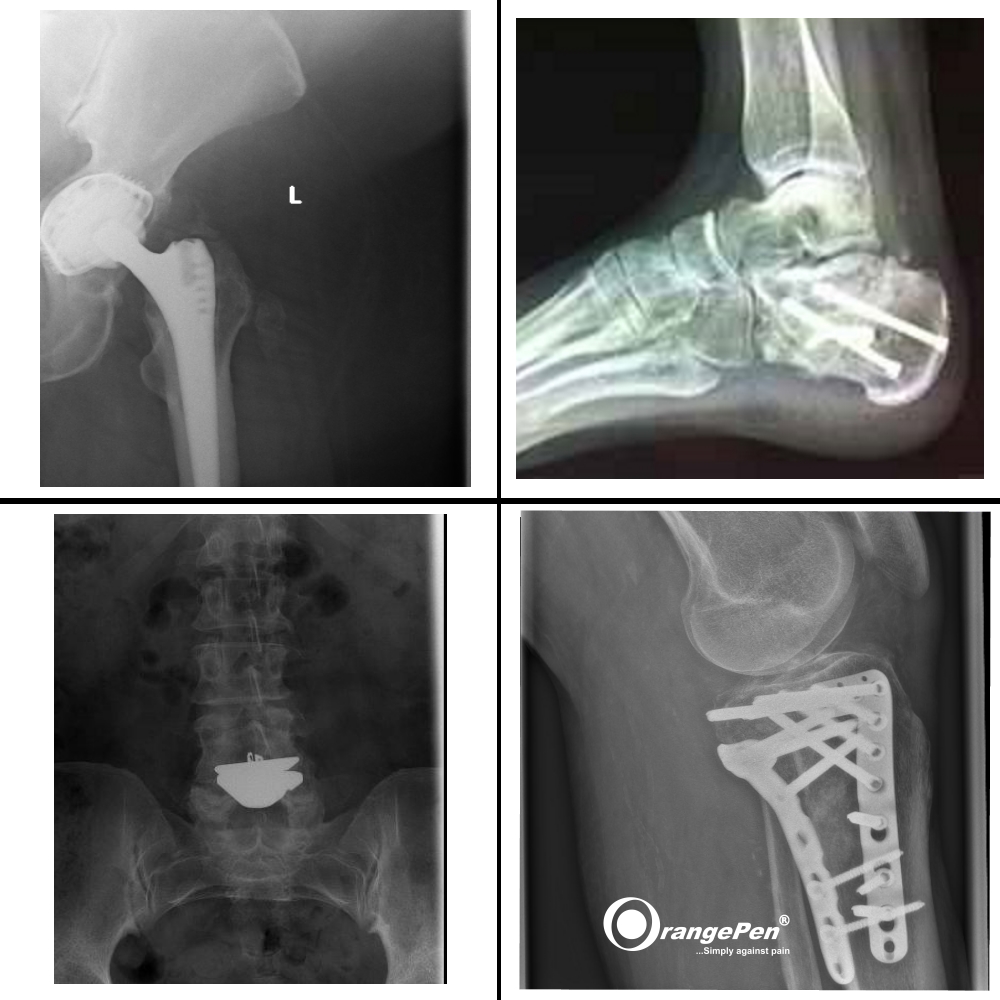

Metal Implants

Metal Implants treated with OrangePen®

For the OrangePen it is of secondary importance whether there is metal in the body. Only the treatment time must be adapted to the new requirements. Even pacemaker patients have been treated successfully.